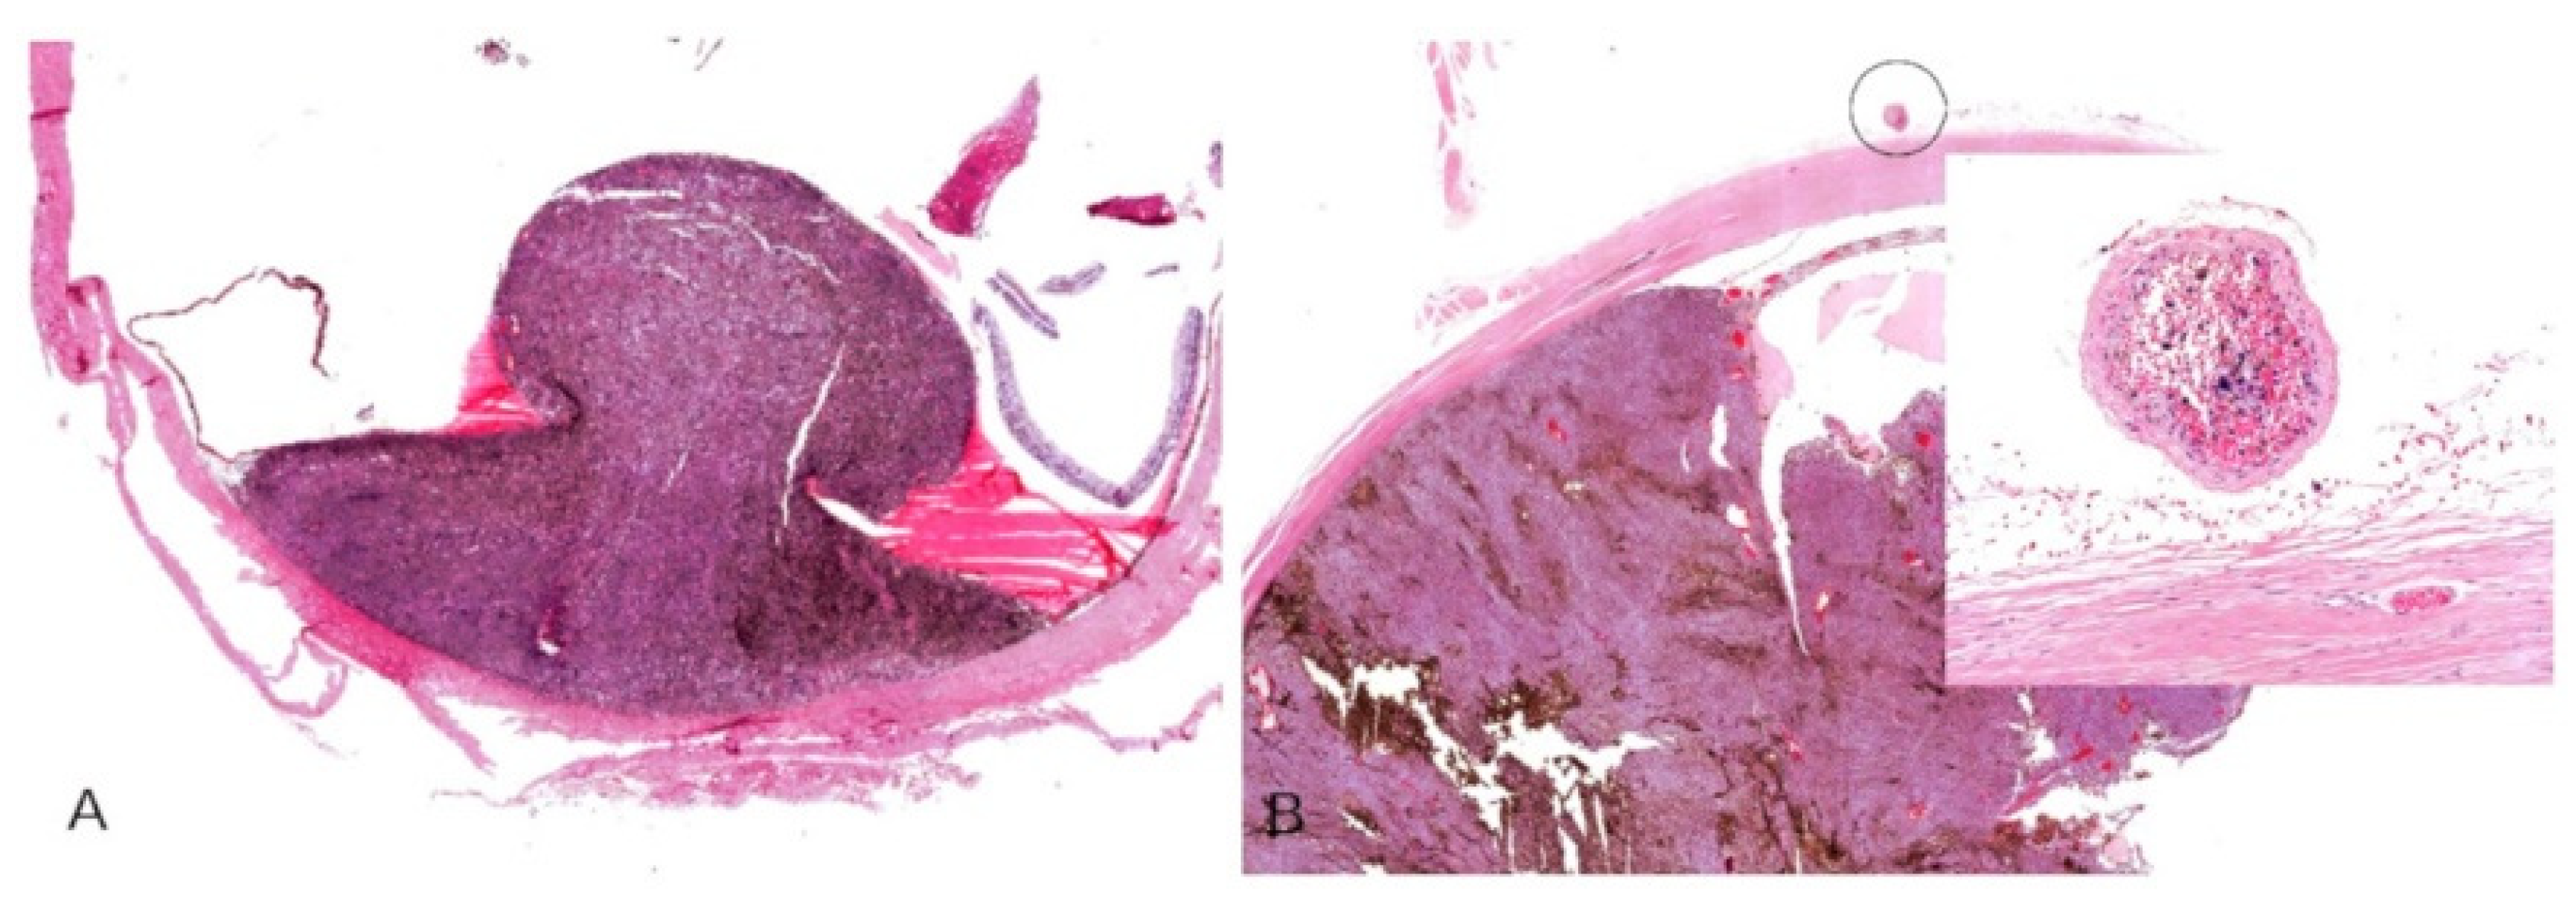

The enucleated eyes were fixed in formalin (10%) for at least 48 h, sliced into sections (Figure 1A), and embedded in paraffin (Figure 1B). Subsequently, 5 µm thick sections were prepared and mounted on glass slides for dewaxing with xylene. They were then rehydrated with ethanol and distilled water. The sections were stained with hematoxylin and eosin (H&E) according to usual protocols and assessed by two pathologists under a stereomicroscope with transmitted light.

Figure 1.

(A) Three slices of a formalin fixed enucleated eyeball with uveal melanoma. (B) An eyeball sample embedded in paraffin.